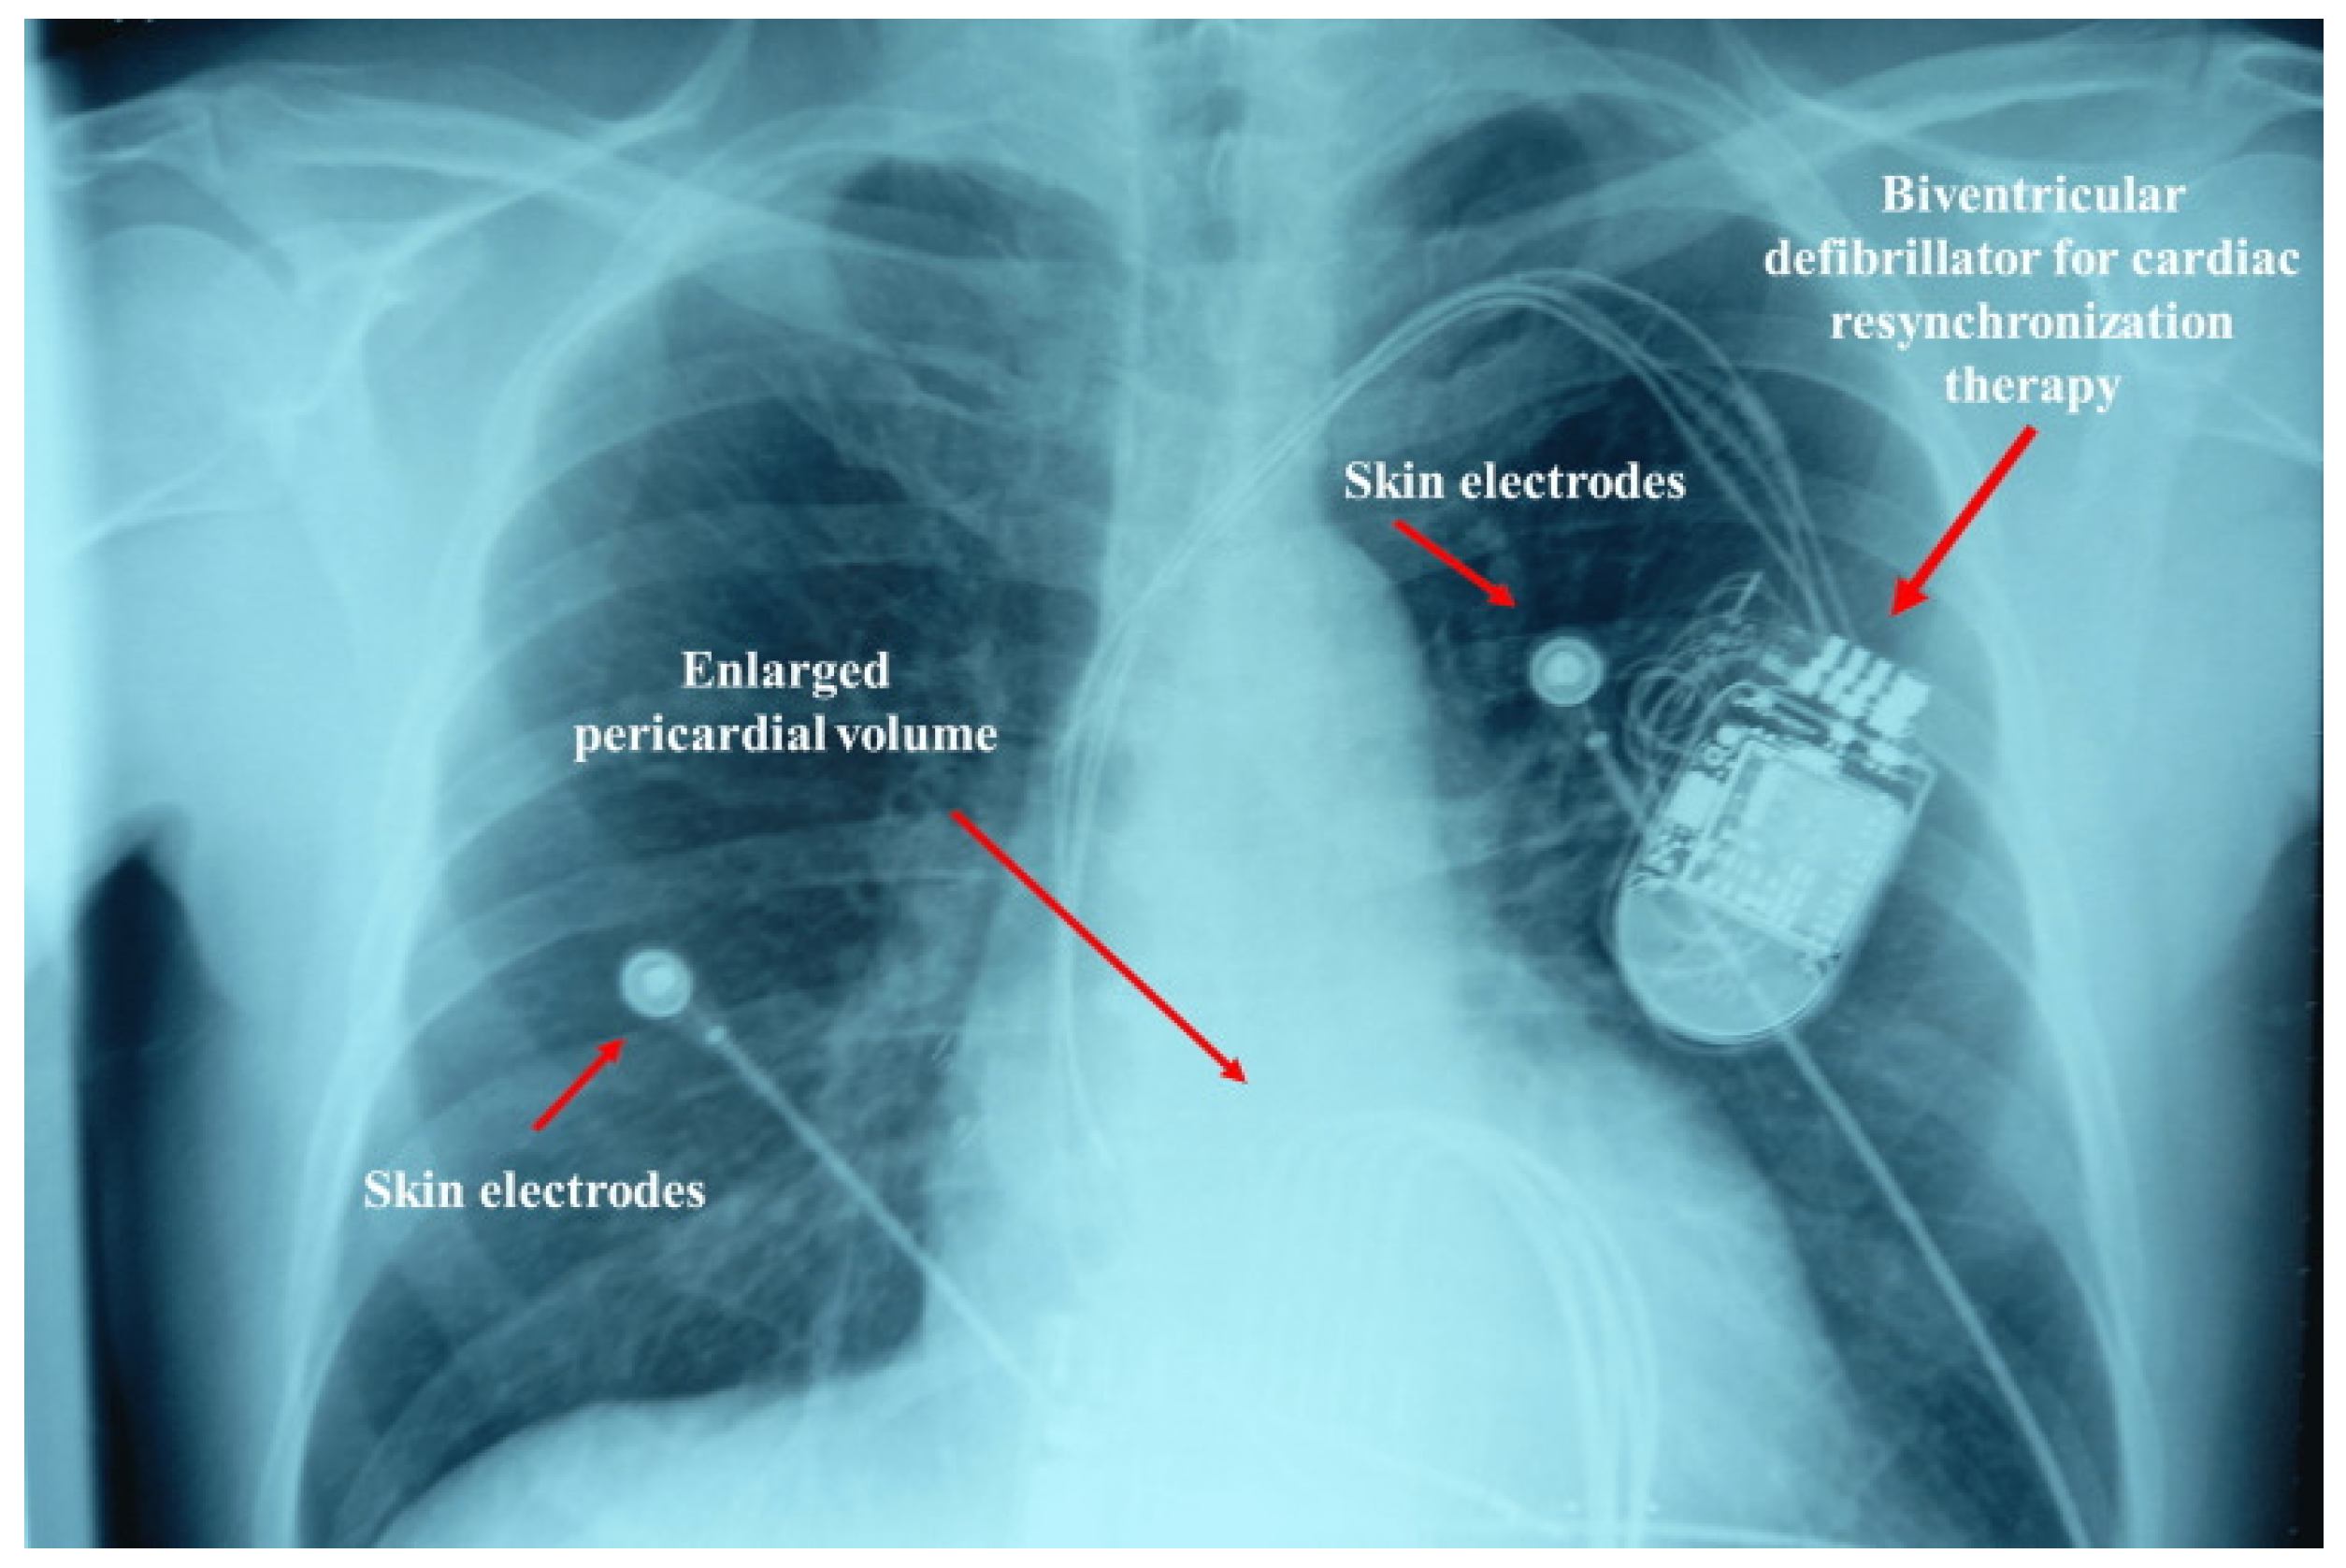

- Bordoni, B.; Morabito, B.; Myftari, V.; D’Amato, A.; Severino, P. Chronic Heart Failure Rehabilitation: Diaphragm Training Needs More Attention. J. Clin. Med. 2025, 14, 5624. [Google Scholar] [CrossRef] [PubMed]